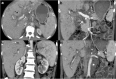

Objectives: We aim to illustrate the multimodal imaging spectrum of hepatic involvement in tuberculosis (TB). Whilst disseminated tuberculosis on imaging typically manifests as multiple small nodular lesions scattered in the liver parenchyma, isolated hepatic tuberculosis remains a rare and intriguing entity.

Methods: Indubitably, imaging is the mainstay for detection of tubercular hepatic lesions which display a broad spectrum of imaging manifestations on different modalities. While sonography and computed tomography (CT) findings have been described in some detail, there is a paucity of literature on magnetic resonance imaging (MRI) features. Due to a significant overlap with other commoner and similar appearing hepatic lesions, hepatic tuberculosis is often either misdiagnosed or labelled as indeterminate lesions. This article is a compendium of cases highlighting the spectrum of imaging patterns that can be encountered in patients with isolated primary hepatic tuberculosis as well as disseminated (secondary) disease. Rare patterns of primary disease such as tubercular cholangitis, hypervascular liver masses, and those with vascular complications are also illustrated and discussed.

Teaching points: • Hepatic TB has myriad imaging manifestations and is often confounded with neoplastic lesions. • Imaging patterns include miliary TB, macronodular TB, serohepatic TB and tubercular cholangitis. • Concurrent splenic, nodal or pulmonary involvements are helpful pointers towards the diagnosis. • Miliary calcifications along the bile ducts are characteristic of tubercular cholangitis. • Histological/microbiological confirmation is often necessary to confirm the diagnosis.